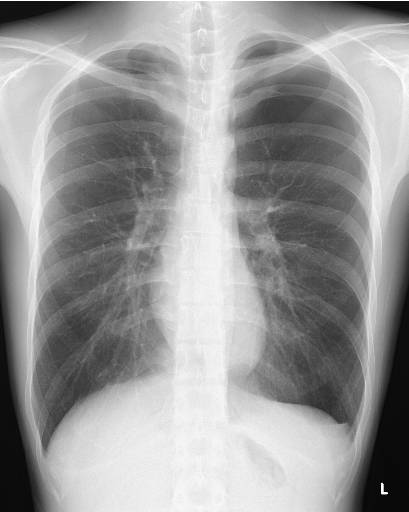

Fig.1 Result of X-ray analysis on MIYATANI.